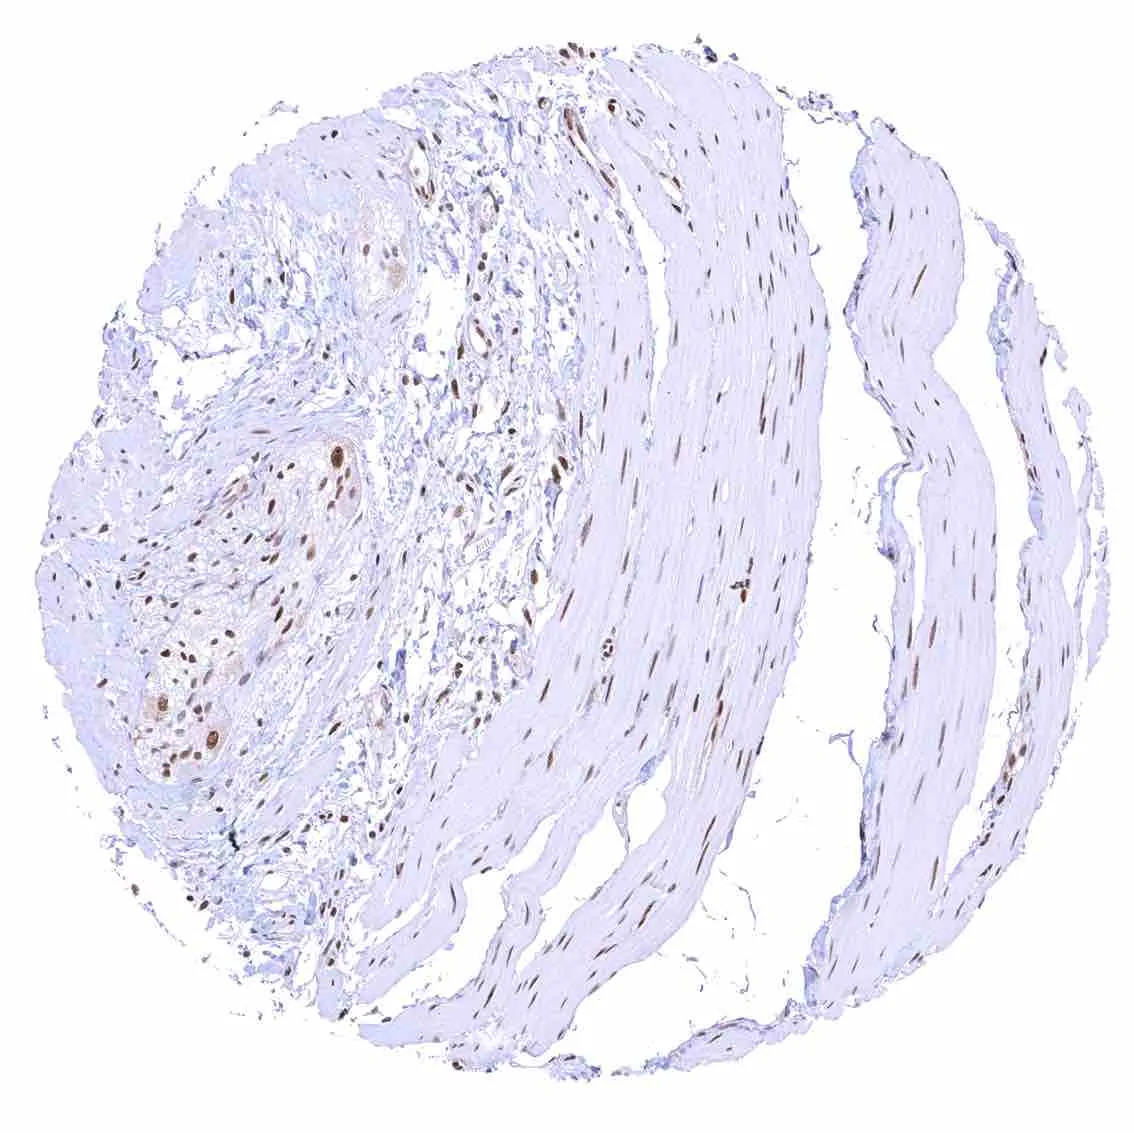

Uterus, myometrium – Nuclear p27 staining of variable intensity in most muscle cells.